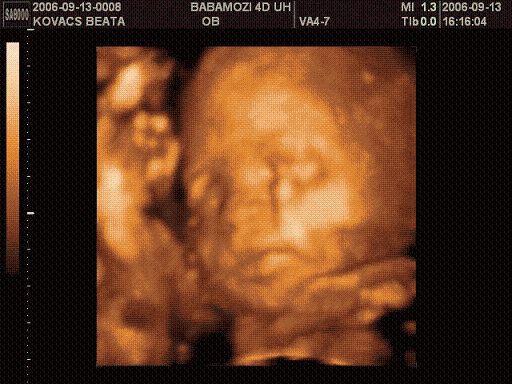

Bea!

Ma mész 4D-re ugye? Várjuk ám a képeket Ádikáról. Azt hallottam, hogy emailen elküldik neked ha kéred.